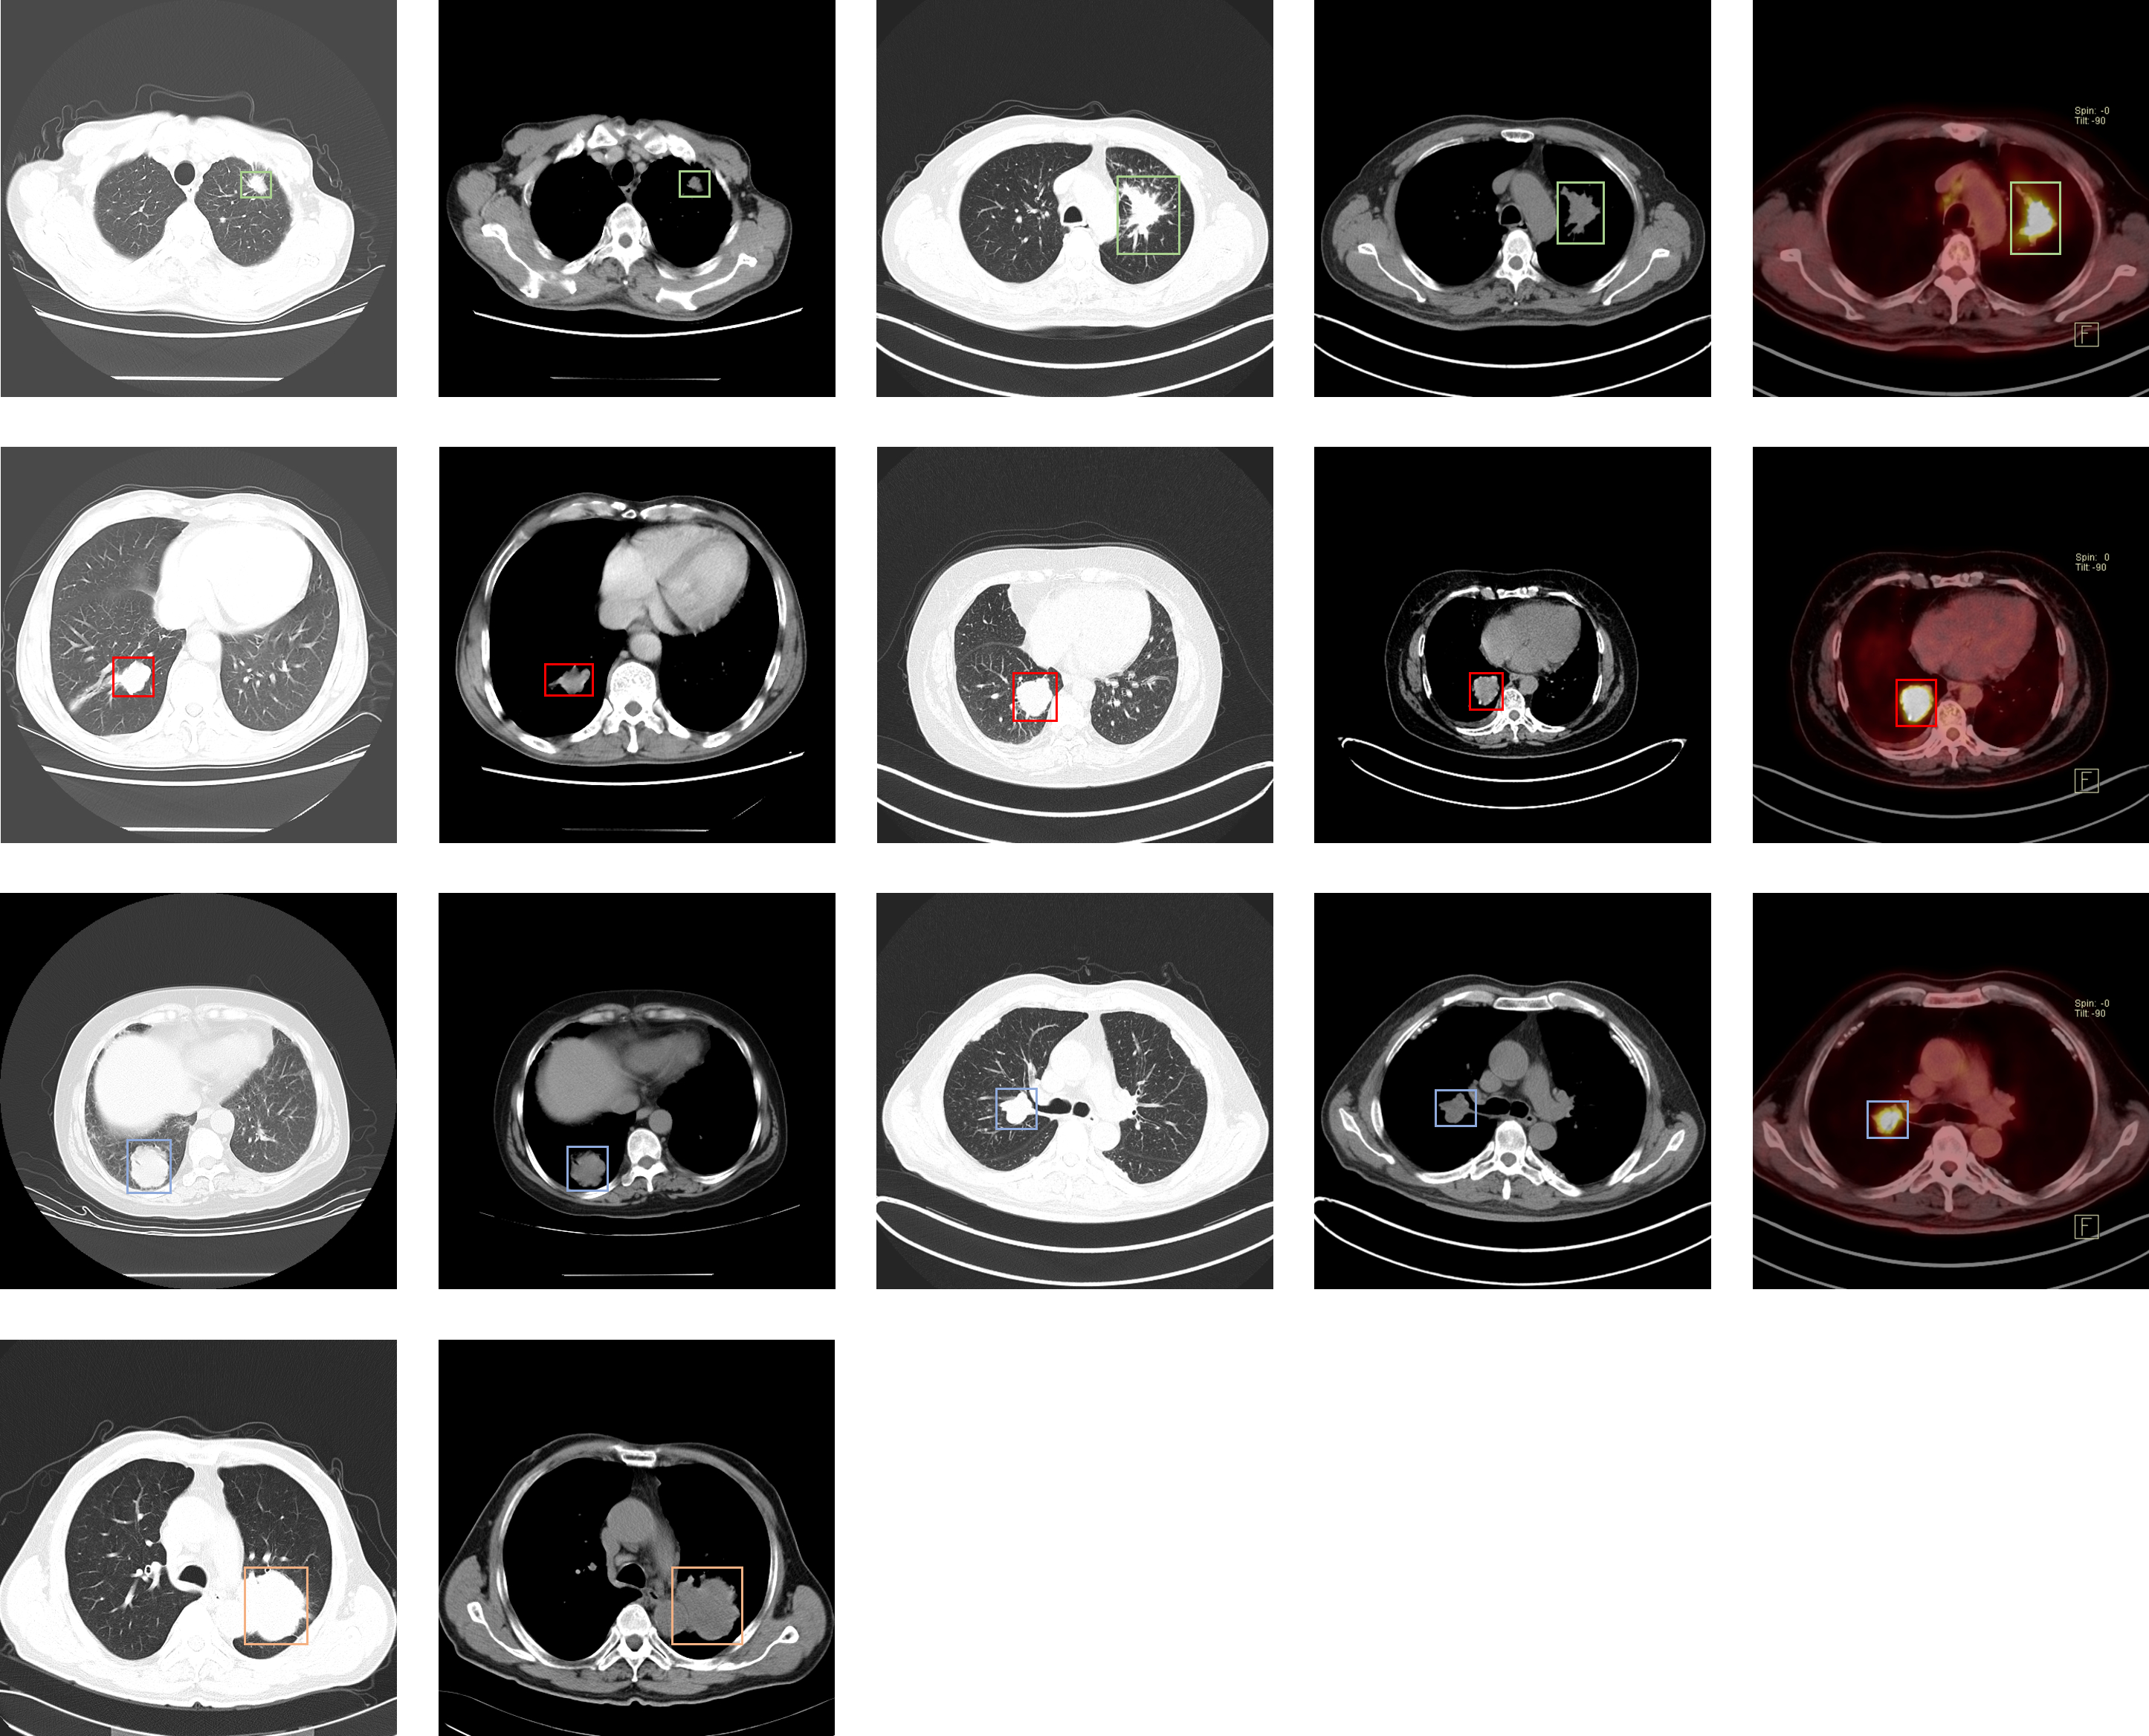

## 肺结节

### LIDC-IDRI

| [LIDC-IDRI](https://wiki.cancerimagingarchive.net/display/Public/LIDC-IDRI) | 肺部肿瘤 | 目标检测 | CT | 1012 | xls | dcm |

介绍论文: [The Lung Image Database Consortium (LIDC) and Image Database Resource Initiative (IDRI): A Completed Reference Database of Lung Nodules on CT Scans](https://www.ncbi.nlm.nih.gov/pmc/articles/PMC3041807/)

### LUNA16

| [LUNA16](https://luna16.grand-challenge.org) | | | | | | |

### 天池肺部结节

| [天池肺部结节](https://tianchi.aliyun.com/competition/entrance/231601/introduction) | | | | | | |

### LNDB

| [LNDB](https://lndb.grand-challenge.org) | 直径大于3mm的肿瘤分割标注/小于3mm肿瘤和非肿瘤标记中心 | 分割/分类 | CT | 294 | XML | MetaImage |

介绍论文: [LNDb: A Lung Nodule Database on Computed Tomography](https://arxiv.org/abs/1911.08434)

### Lung Nodule Malignancy

| [Lung Nodule Malignancy](https://www.kaggle.com/kmader/lungnodemalignancy) | 肺结界良恶性 | 分类 | CT | 4165+2526 | | tif |

### Data Science Bowl 17

| [Data Science Bowl 17](https://www.kaggle.com/c/data-science-bowl-2017) | | | | | | |

### Lung-PET-CT-Dx

| [Lung-PET-CT-Dx](https://wiki.cancerimagingarchive.net/pages/viewpage.action?pageId=70224216) | 肺癌 | 目标检测 | CT | 363 | xml | dcm |